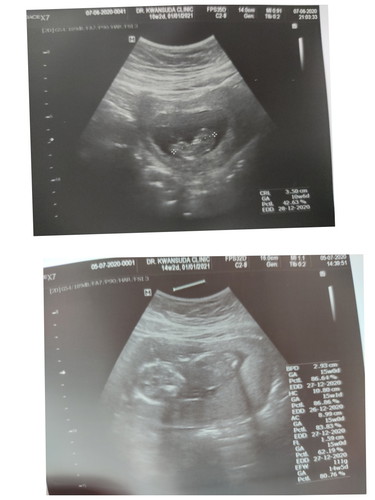

เดือนที่แล้วหันหัวทางนึง เดือนนี้หันกลับมาอีกทาง กลับหัวกลับหางเลยอะค่ะ เปนไรไหมคะ ลืมสังเกตตั้งแต่ตอนอยู่กับหมอ มัวแต่ตื่นเต้นพัฒนาการเขา